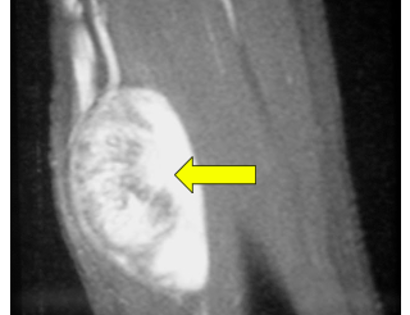

This is an example of a schwannoma, a common benign soft-tissue mass, located in the patient's arm.

This is an intraoperative photo of a schwannoma, a common benign soft-tissue tumor.